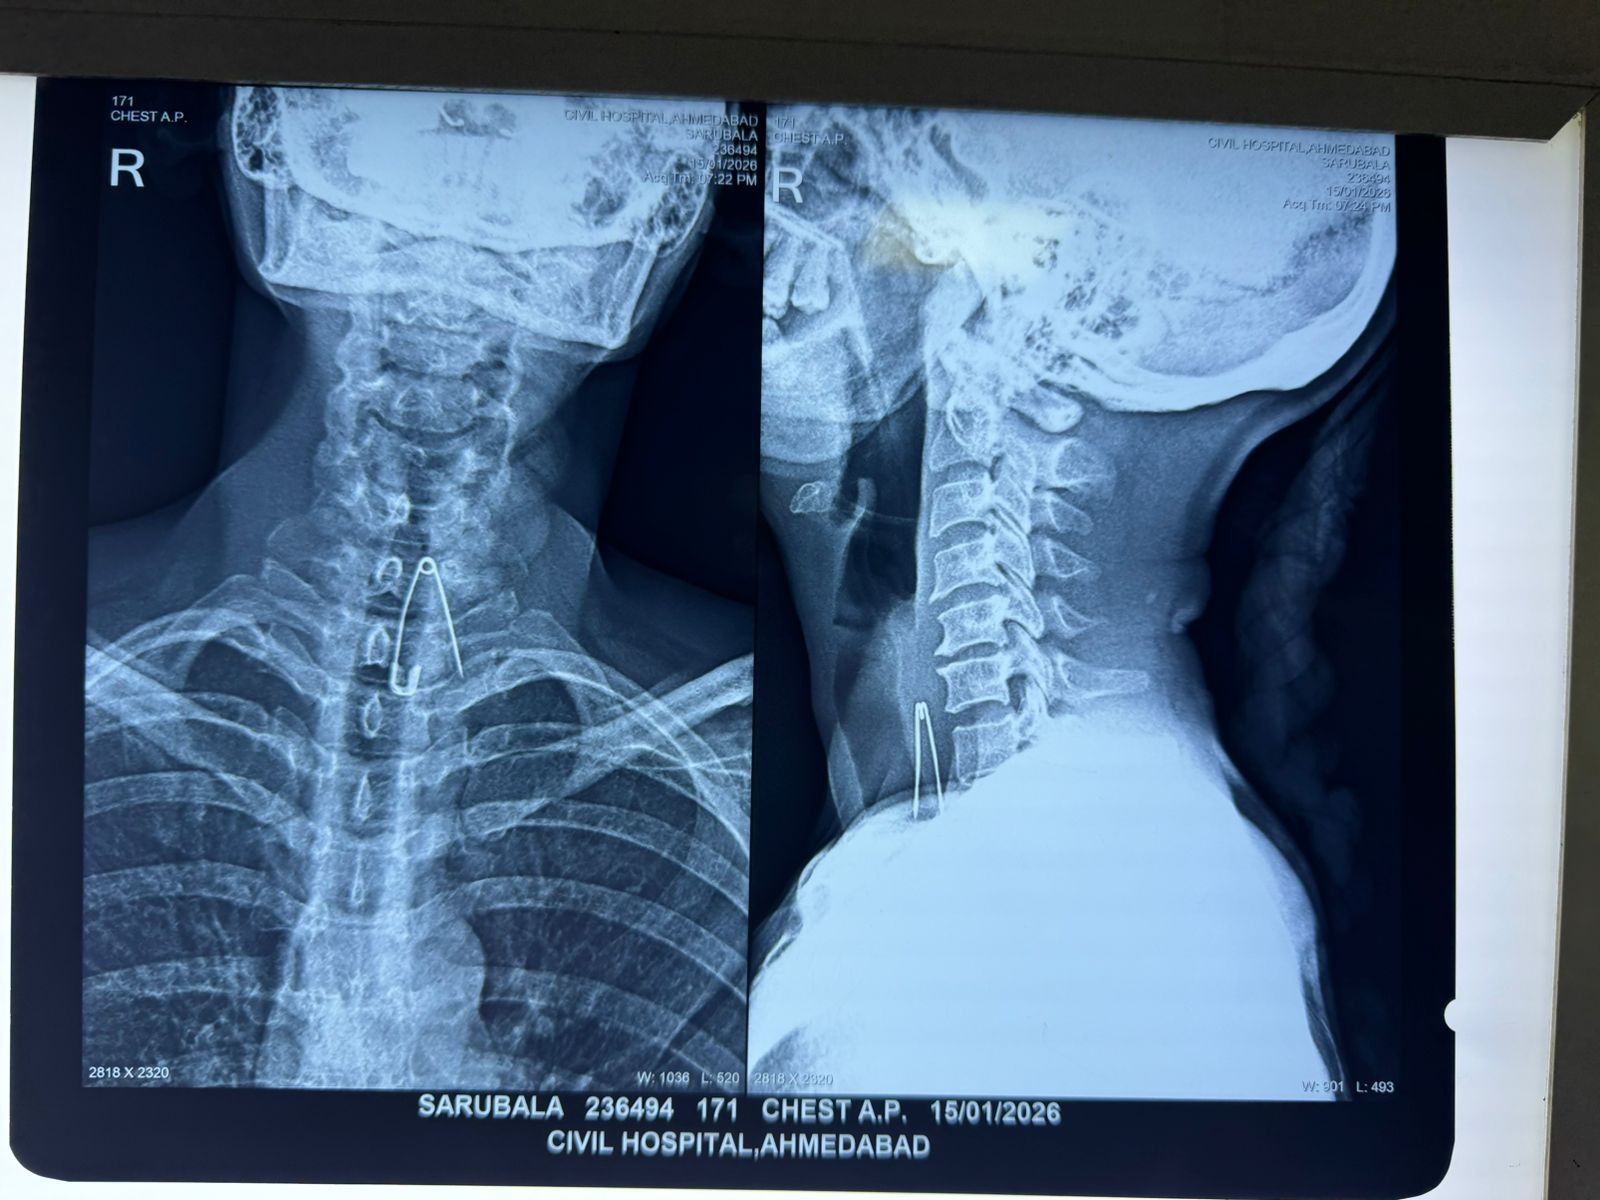

સિવિલ હોસ્પિટલના ઈએનટી વિભાગના વડા ઈલા ઉપાધ્યાય આ કેસની વધુ વિગતો આપતા જણાવ્યું કે, એક ૪૮ વર્ષીય મહિલા દર્દી સરૂબાલા રમેશચંદ્રને સિવિલના ઈમરજન્સી વિભાગમાં તારીખ ૧૫ જાન્યુઆરીના રોજ વીસ દિવસ પહેલા ગળામાં સેફ્ટી પીન ગળી જવાની તકલીફ સાથે દાખલ કરાયા હતા. દર્દી પાસેથી હિસ્ટ્રી જાણતા માલૂમ પડ્યું, કે દર્દી ખેંચની બીમારીથી પીડિત હતું. આશરે ૨૦ દિવસ પહેલા સેફટી પીન વડે દાંત સાફ કરતી વખતે અચાનક ખેંચ આવતા સેફટી પીન ગળી ગયા હતા. દર્દીનો એક્સરે કરાવતા દર્દીના ઝ્ર-૭ અને ્-૧ મણકાના લેવલે અન્નનળીમાં સેફ્ટી પીન ફસાઈ હોવાનું અમને દેખાયું હતું. તેઓએ આગળ કહ્યું કે, સેફટી પીન ગળામાં ફસાઈ જવાથી આંતરિક ઇજાનો ગંભીર ખતરો હતો અને વિલંબ જીવલેણ સાબિત થઈ શકે તેમ હતું. તારીખ ૧૬ જાન્યુઆરીના રોજ સિવિલના ઈએનટી વિભાગના વડા ડોક્ટર ઇલા ઉપાધ્યા તેમજ એનેસ્થસિયા વિભાગના ડો. ભાવના રાવલની ટીમ દ્વારા મહામહેનતે ઈસોફેગોકોપી કરી સફળતાપૂર્વક અન્નનળીના બીજા કોઈ પણ ભાગને ઈજા થયા વગર સેફટી પીન મહિલાના શરીરમાંથી બહાર કાઢવામાં આવી હતી.